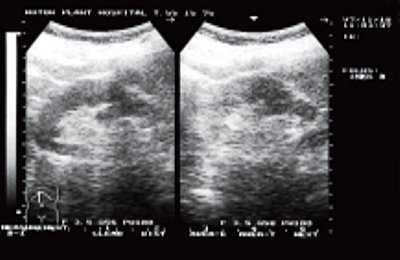

В большинстве случаев (75% больных) опухолевый участок при ТРУЗИ был гипоэхогенным и локализовался в периферической зоне. У одного пациента определялся гипоэхогенный участок, захватывающий периферическую и центральную части. У двух пациентов, используя стандартные методики ТРУЗИ, нельзя было установить границу между нормальной и опухолевой тканью. В нашем исследовании прорастание опухолью стенки мочевого пузыря выявлено у трех пациентов (стадия Т4) (рис.1); прорастание рака предстательной железы в семенные пузырьки определялось у 4 больных (стадия Т3b) (рис.2); капсула прослеживалась на всем протяжении у 11 пациентов с раком предстательной железы (стадия Т2) (рис. 3а); у двух пациентов целостность капсулы была нарушена (стадия Т3а) (рис. 3б). Степень распространения опухоли определяла тактику лечения.

Рис. 2. Прорастание рака предстательной железы в семенной пузырек. Определяется расширенный, гипоэхогенный семенной пузырек слева. Поперечный срез на уровне семенных пузырьков.